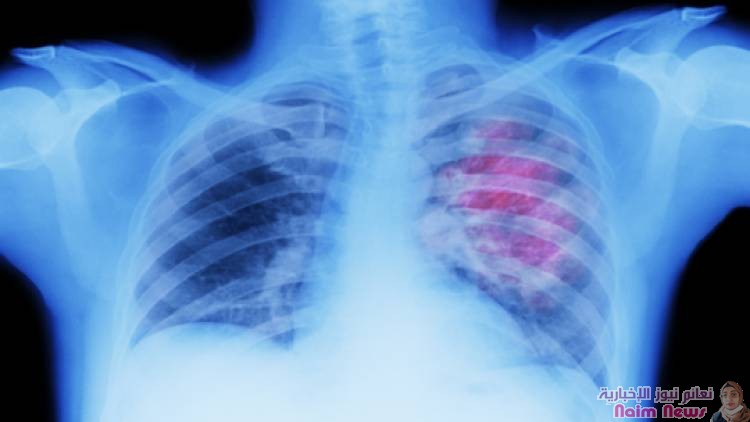

علامات لسرطان الرئة يمكن رؤيتها على الوجه!

حذر خبراء من أن تورم الوجه قد يكون علامة رئيسية على الإصابة بسرطان الرئة.

ويمكن أن يحدث تورم الوجه، على الرغم من أن هذا السبب أقل شهرة، عندما يمارس الورم ضغطا على الوريد الأجوف العلوي (SVC)، الذي يربط الرأس بالقلب. وتجعل الجدران الرقيقة لهذا الوريد الحيوي عرضة للضغط.

ووفقا لـ Macmillan Cancer Support، فإن معظم حالات انسداد الوريد الأجوف العلوي (SVCO) ناتجة عن سرطان الرئة.

ويقولون: "معظم حالات SVCO (انسداد الوريد الأجوف العلوي) ناتجة عن سرطان الرئة. قد يضغط السرطان مباشرة على SVC. أو قد ينتشر إلى الغدد الليمفاوية القريبة، والتي تصبح منتفخة. وهناك أسباب أخرى محتملة: سرطانات أخرى تصيب الغدد الليمفاوية في الصدر. وتشمل هذه الأورامَ اللمفاوية وسرطانَ الخصية والثدي والأمعاء والمريء. فتتشكل جلطة دموية في الوريد وتعوق تدفق الدم. يمكن أن يحدث هذا إذا كان لديك (خط مركزي) في الوريد - على سبيل المثال، لإعطائك علاجا كيميائيا".

وبالإضافة إلى تورم الوجه، قد يعاني الأفراد أيضا من تورم في الرقبة والذراعين وأعلى الصدر بسبب ضغط الوريد. وقد تشمل الأعراض المصاحبة الأخرى ضيق التنفس، أو الصداع، أو تغيرات في البصر، أو ظهور أوردة زرقاء على الصدر، أو الدوخة.

ويسلط موقع NHS الإلكتروني الضوء على أن سرطان الرئة نادر الحدوث لدى من تقل أعمارهم عن 40 عاما، ويؤثر في الغالب على كبار السن.

وفي حين أن غير المدخنين يمكن أن يصابوا بسرطان الرئة، فإن التدخين هو السبب الرئيسي، حيث يمثل أكثر من 70% من الحالات. ويساهم الاستنشاق المنتظم للمواد السامة المختلفة من خلال التدخين في زيادة المخاطر.

وبالنسبة للمدخنين، يعد الإقلاع عن هذه العادة خطوة حاسمة في تقليل فرص الإصابة بسرطان الرئة.